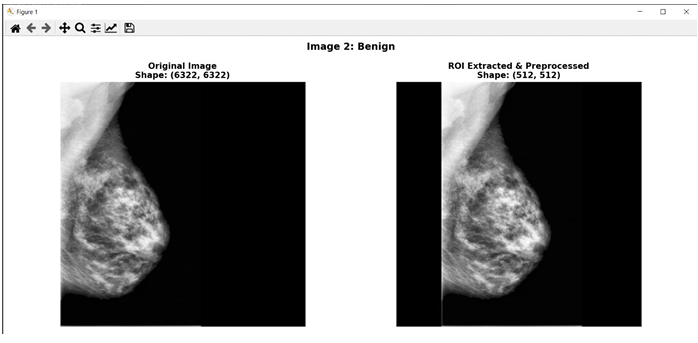

Full-stack AI web app for mammography-based breast cancer detection using a fine-tuned Swin Transformer on CBIS-DDSM, achieving 87.5% accuracy with dual-view ensemble analysis.

- Built a full-stack AI web application for breast cancer detection using a fine-tuned Swin Transformer trained on the CBIS-DDSM mammography dataset (~30,000 images), achieving 87.5% accuracy and 0.884 ROC-AUC.

- Applied transfer learning with an ImageNet-pretrained Swin Transformer, class weighting to address dataset imbalance, and augmentation techniques (flips, rotations, contrast jitter) for robust generalization.